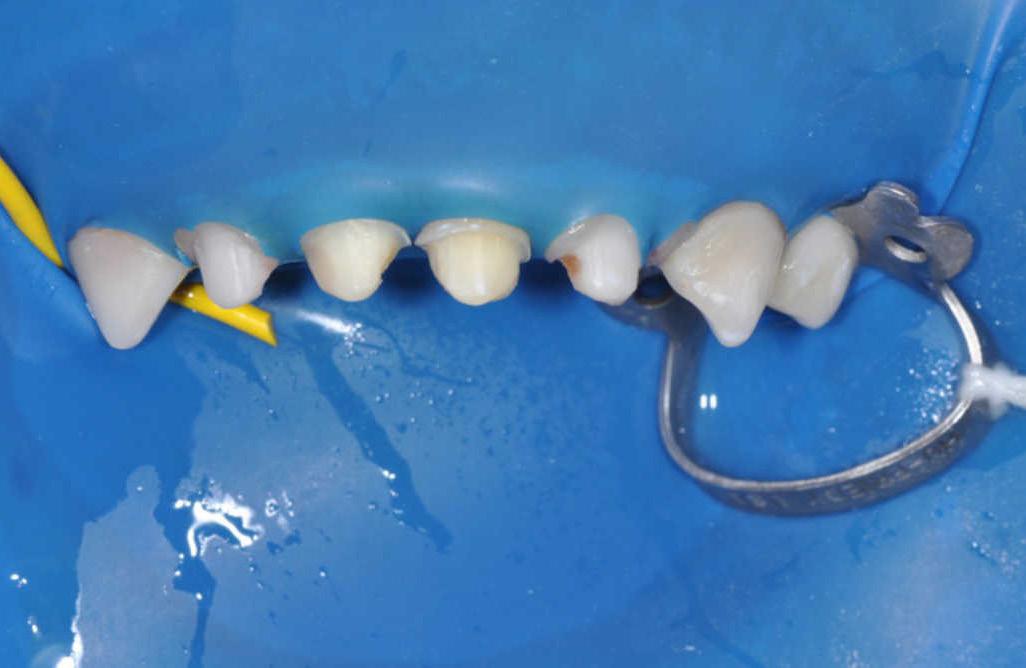

Case 1: Anterior tooth restoration with composite

Case 2: Posterior tooth restoration with composite

Restorations with Beautifil II LS, Beautifil Flow Plus X and OneGloss by Erik-Jan Muts, M.Sc., Netherlands